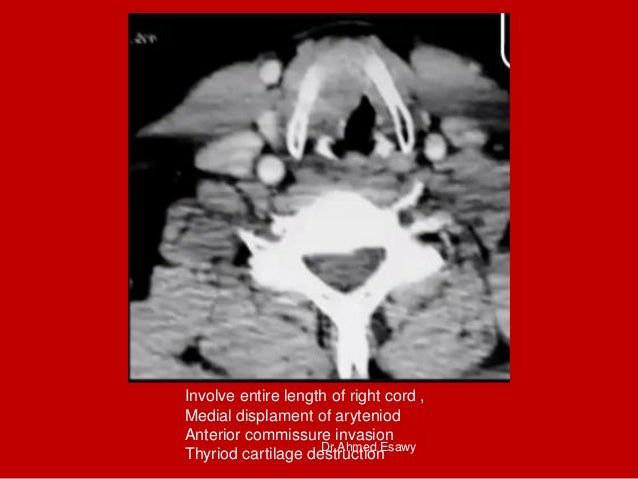

32. 32. Involve entire length of right cord , Medial displament of aryteniod Anterior commissure invasion Thyriod cartilage destructionDr Ahmed Esawy